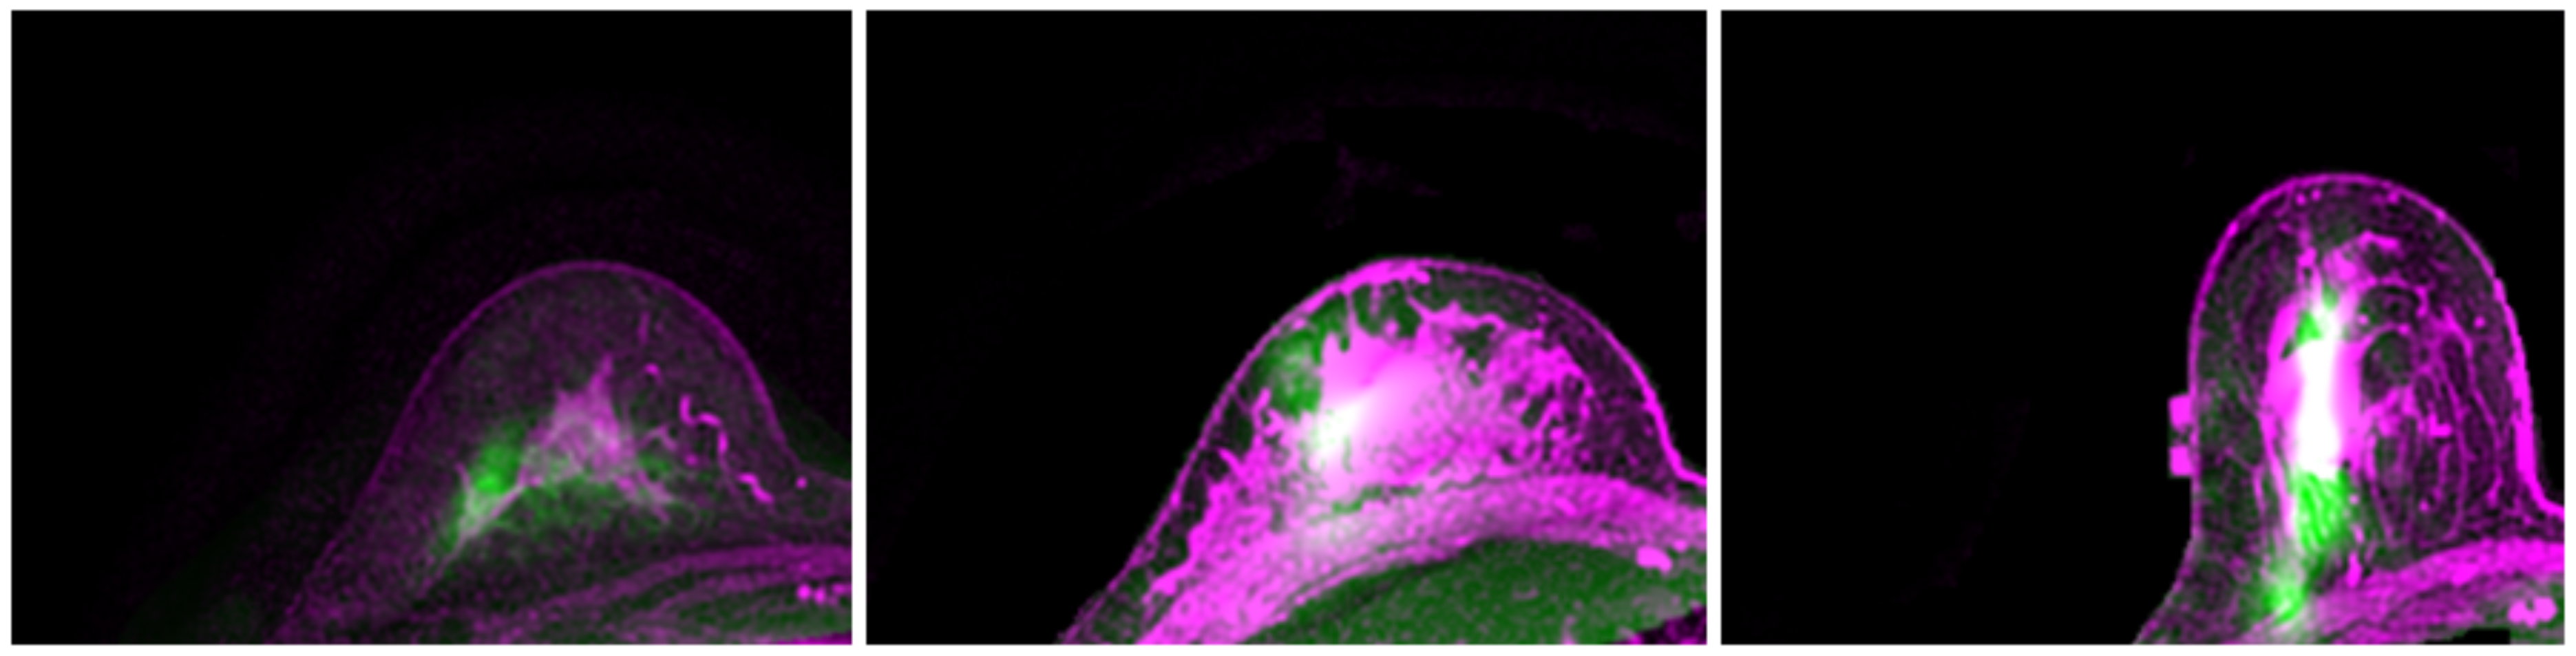

2.3. Optimization and Registration

3.1. Model Performance

3.2. Registration Error